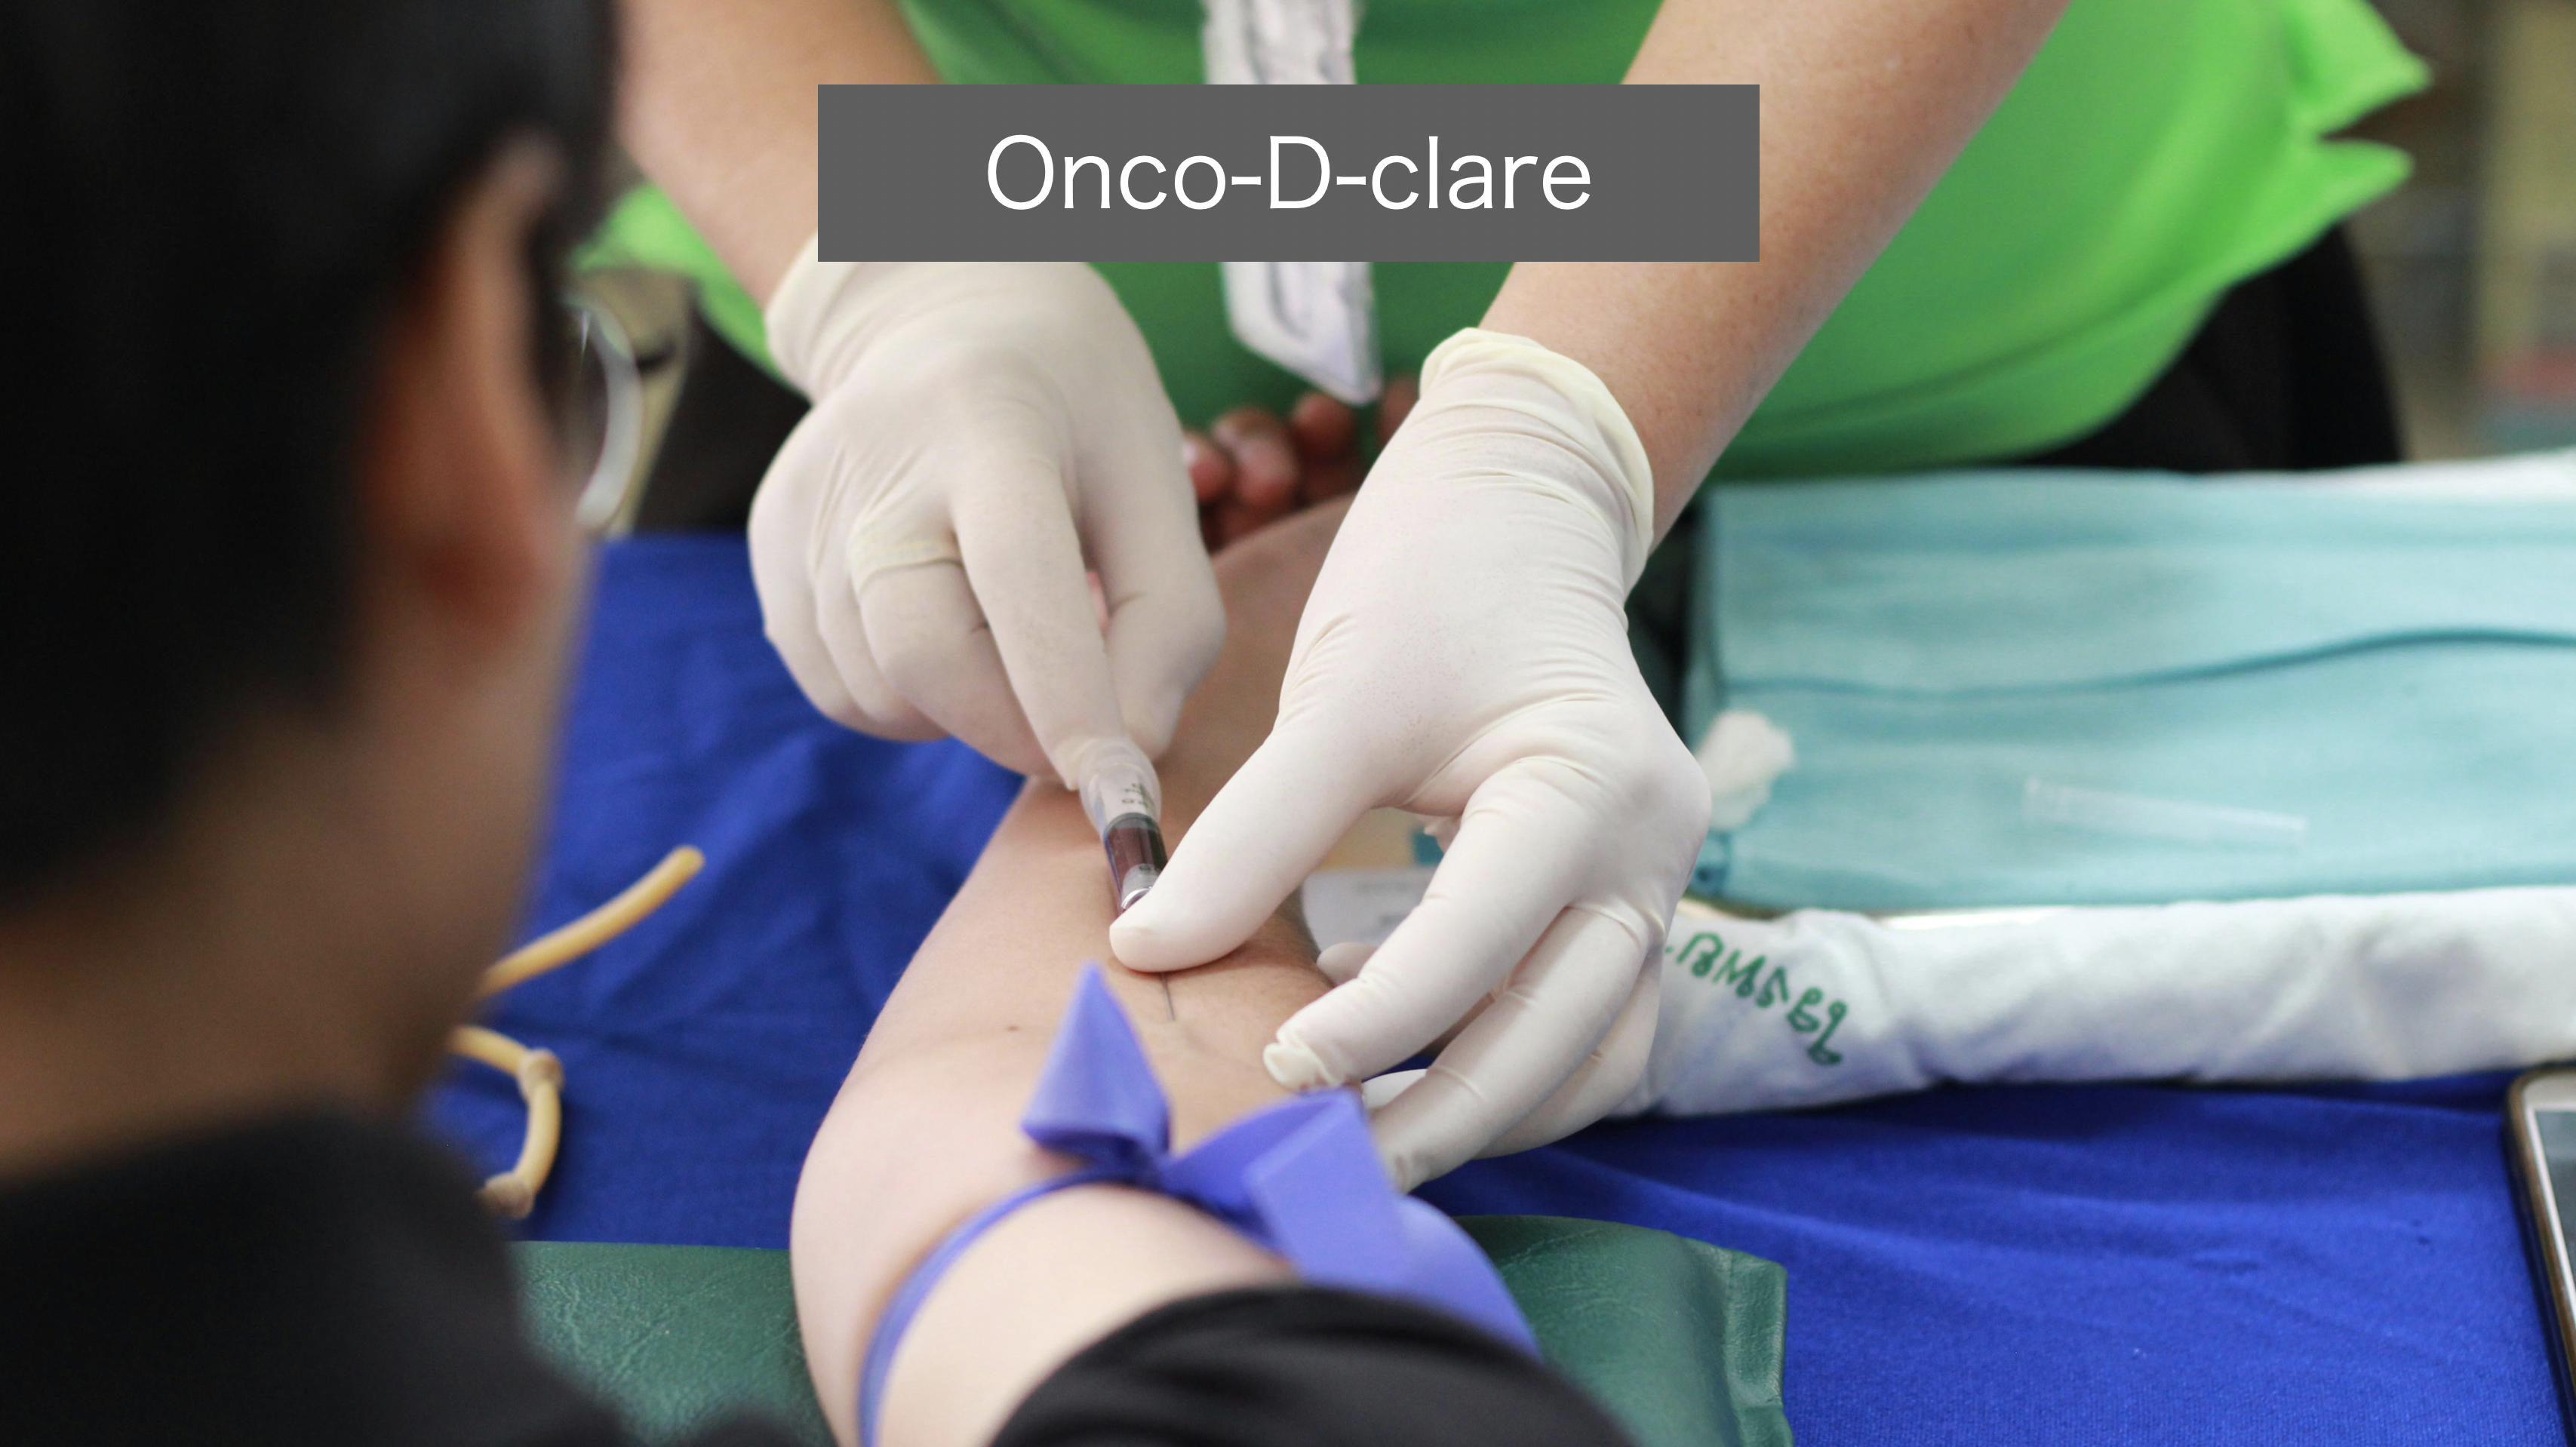

細胞を一切刺激しない口腔がん検診 オンコ-D-クレア (Onco-D-clare) 検査の導入

本邦においても2024年から、Onco-D-clareが利用できるようになりました。

この検査は、病変部位に一切の刺激を加える事なく、わずか5-8mlの血液を腕から採血する事で検査ができます。

得る事ができた免疫細胞のガン発症に伴う遺伝子発現パターンを人工知能 (AI) にて解析します。

この方法は、超早期、すなわち、まだ ”がん” として成立していない段階が適応です。

本邦においても2024年から、Onco-D-clareが利用できるようになりました。

この検査は、病変部位に一切の刺激を加える事なく、わずか5-8mlの血液を腕から採血する事で検査ができます。

得る事ができた免疫細胞のガン発症に伴う遺伝子発現パターンを人工知能 (AI) にて解析します。

この方法は、超早期、すなわち、まだ ”がん” として成立していない段階が適応です。